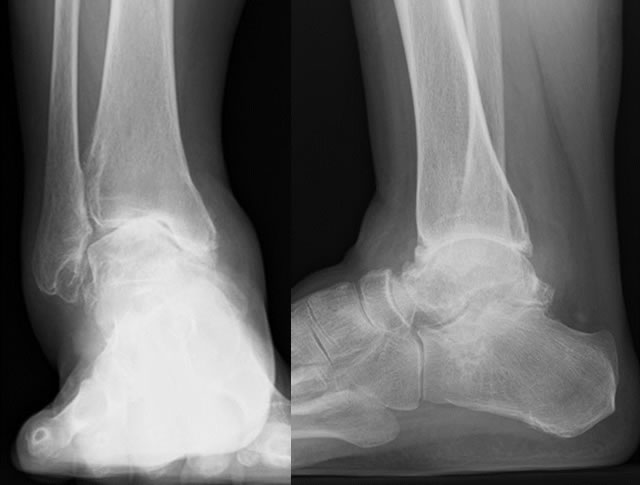

2.内反型変形性足関節症に対する鏡視下足関節固定術

術前

術後

術後10日、ヒール付きギプス固定で全荷重歩行開始

術後2カ月、ギプスから着脱可能な装具(サポーター)に変更

術後4カ月頃、骨癒合を確認し装具終了